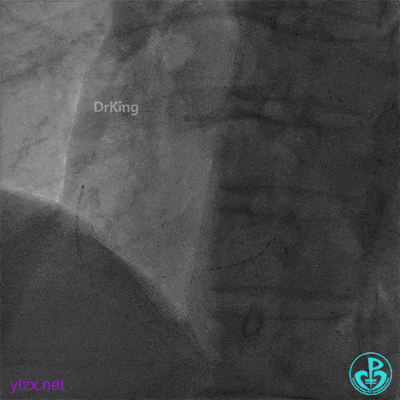

急诊冠脉造影

粗大前降支中段严重狭窄,血流3级。

粗大右冠脉中段严重狭窄,血流3级。